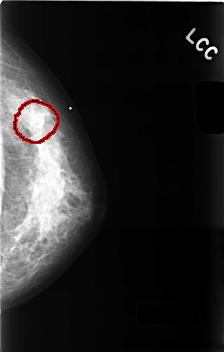

C_0494_1.LEFT_CC

LEFT_CC LINES 4568 PIXELS_PER_LINE 2912 BITS_PER_PIXEL 12 RESOLUTION 50 OVERLAY

FILE: C_0494_1.LEFT_CC.OVERLAY

TOTAL_ABNORMALITIES 1

ABNORMALITY 1

LESION_TYPE MASS SHAPE OVAL MARGINS OBSCURED

ASSESSMENT 3

SUBTLETY 1

PATHOLOGY BENIGN

TOTAL_OUTLINES 1

BOUNDARY